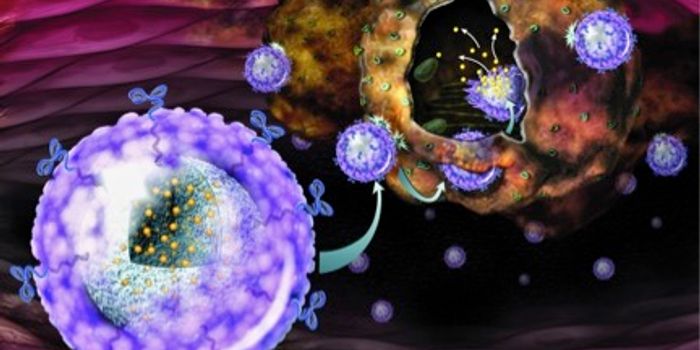

MAR 02, 2023CancerImmunotherapies, cancer treatments that target the immune system, have drastically improved patient care over the past d ...